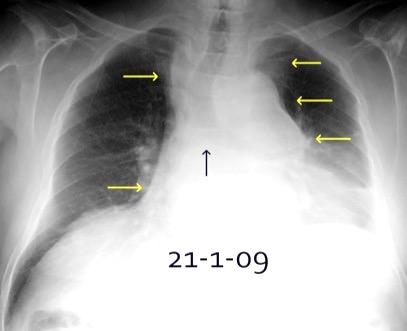

Triada de Garland

Ganglios paratraqueales derechos e hiliares bilaterales

95% de pacientes tienen ganglios hiliares bilaterales aislados o con afectación mediastínica (espec. paratraqueal derecho).

Criado E et al. Pulmonary sarcoidosis: typical and atypical manifestations at high-resolution CT with pathologic correlation. Radiographics. 2010